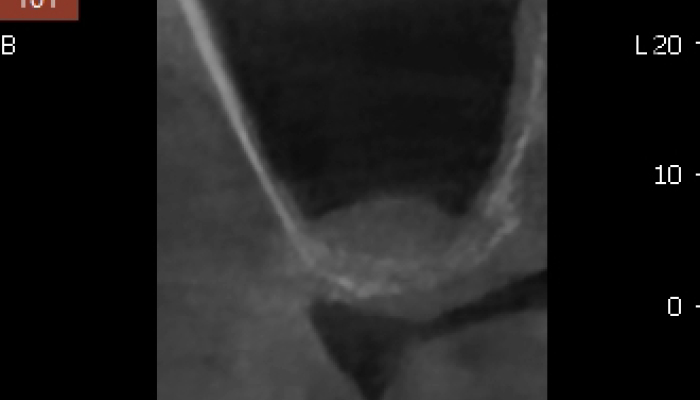

임플란트 시술을 위한 정밀진단

치아를 뺴고 오래 방치하거나 치아를 잡고 있는 치조골이 많이 녹은상태에서 치아를 빼면 위쪽 턱뼈가 부족할 수 있습니다.